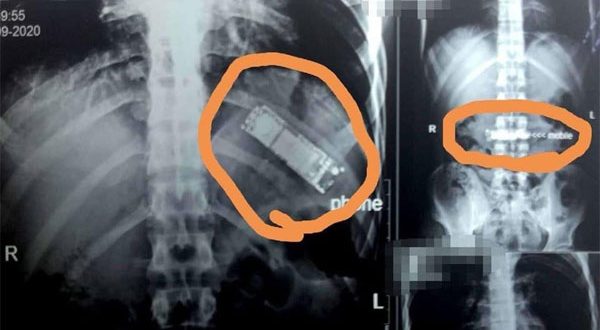

في حادثة غريبة، تمكن فريق طبي في مصر من استخراج هاتف محمول من معدة مواطن مصري كان قد ابتلعه منذ 7 أشهر.

ووصل المواطن حسن رشاد البالغ 28 عاماً إلى مستشفى بنها الجامعي، حيث كان يشكو من آلام بمعدته تعاوده من فترة لأخرى، وبفحصه وإجراء اللازم تبين وجود جسم غريب داخل بطنه.

كما أظهرت الفحوصات أن هذا الجسم الغريب هو هاتف جوال فيما قال المريض إنه ابتلعه خلال لحظة مزاح بينه وبين زملائه، لافتاً إلى أنه لم يبلغ أسرته بالواقعة ظناً منه أنه وبمجرد أن يقوم بالقيء في أي وقت سيتمكن من إخراج الهاتف من معدته.

وأجرى الفريق الطبي جراحة عاجلة للمريض استغرقت ساعتين واستخرج الهاتف من معدته.

إلى ذلك اعتبر أن “القدر كان رحيماً بالمريض حيث لم تتحلل البطارية وتتفاعل داخل جسمه وتصيبه بالتسمم”، مضيفاً أنه كان من الممكن أن تنفجر البطارية أو تتحلل داخل معدة الشاب وتودي بحياته”.